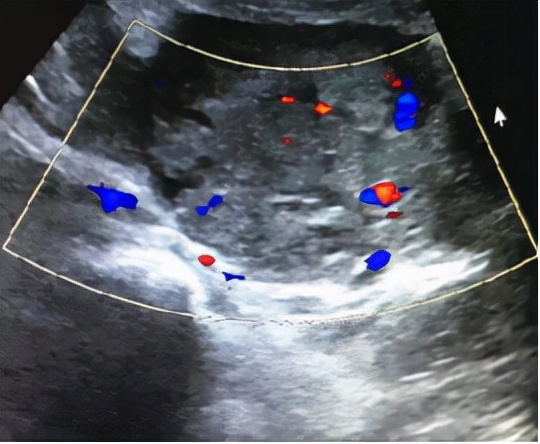

2020年11月9日上午,妇科门诊走进来一位年轻的患者,吴XX,停经2月余,间断少量阴道流血20余天,因阴道流血增多伴左下腹痛来就诊,查B超示:早孕,宫腔积血,左附件区不均质回声(51*37*46mm),盆腔积液。血HCG 125417.00MIU/mL ,孕酮 30.20ng/mL。医生详细询问病史,患者系今年备孕半年未孕,于9月中旬外院促排卵治疗。

这两种可能性都随时可能危及大出血危及患者生命,影响宫内妊娠发育,遂立即予以妇科住院保胎治疗,并密切观察患者生命体征。11.10上午吴女士再次出现持续剧烈左下腹痛,复查B超示:早孕,宫腔积血,左附件区不均质回声(64*49*40mm),盆腔积液。包块较入院明显增大,患者疼痛感明显加重,考虑盆腔存在持续出血,需立即行腹腔镜探查术。医生在向患者及家属交代病情及风险后,急诊在全麻下行腹腔镜探查,术中见盆腔积血约300ml,左侧输卵管壶腹部及伞端增粗约3*4cm,伞端有活动性出血,术中再次医患沟通后行左侧输卵管大部分切除术。剖视标本见机化绒毛组织。术后继续予以药物保胎等对症治疗。

有生育要求,特别是辅助生育治疗后的患者,要尽量保证宝宝在宫内不受影响,早诊断早治疗至关重要。阴道超声是目前诊断HP的最好手段。